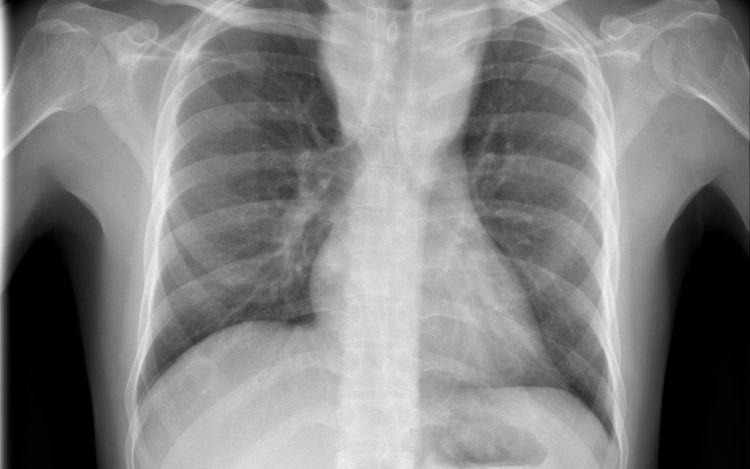

Csökkent a tbc-fertőzések száma Európában

Átlagosan 4,3 százalékkal csökkent az új tuberkulózisos (tbc-s) esetek száma 2010 és 2014 között az Egészségügyi Világszervezet (WHO) 53 országot magába foglaló európai régiójában.

A becslések szerint 2014-ben 340 ezer európai betegedett meg tuberkulózisban, ami százezer emberre vetítve 37 esetnek felel meg. Azzal, hogy 2010 és 2014 között átlagosan 4,3 százalékkal csökkent az új esetek száma, az európai régió teljesítette azt a millenniumi fejlesztési célt, hogy 2015-re visszafordítja a tbc terjedésének tendenciáját.

Magyarországon biztonságos a tbc-re vonatkozó epidemiológiai helyzet: 2014-ben nyolc új eset jutott százezer lakosra, és az előzetes adatok szerint ugyanez igaz a 2015-ös évre is. Így a WHO Magyarországot az alacsonyan átfertőzött országok között tartja nyilván. Alacsony a multirezisztens esetek száma - 2014-ben hét új esetet észleltek -, valamint a gyermekkori megbetegedéseké is: 2014-ben hat 14 éven aluli gyermek betegedett meg.

Az európai régióban ugyanakkor továbbra is nehezíti a tbc felszámolását a multirezisztens tbc és a tbc magas előfordulási aránya a lakosság sérülékeny csoportjaiban (hajléktalanok, kábítószer- és alkoholfüggők, magas fertőzöttségi arányú országokból érkező migránsok) - áll a közleményben. Ezeknek a szegény és marginalizálódott csoportoknak az eléréséhez az ECDC tudományos útmutatást adott ki a közelmúltban.

A WHO a legnagyobb kockázatnak kitett csoportok célzott tbc-szűrését javasolja, Magyarországon 2014 óta eszerint szervezik meg a kötelező tüdőszűrést.